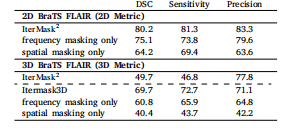

Table 5Ablation study for observing the effect of spatial and frequency masking in the 2D (top) and 3D (bottom) versionsof our model. We also show performance of our 2D model(IterMask2 ) in 3D images from BRATS (bottom) for straightforward comparison with IterMask3D, showing the gainsfrom 3D modeling.

表5 空间掩码与频率掩码作用的消融实验结果 (上表为模型2D版本的实验数据,下表为模型3D版本的实验数据) 此外,为与IterMask3D进行直观对比(以体现3D建模的优势),表中还展示了2D模型(IterMask2D)在BraTS数据集3D图像上的性能表现。